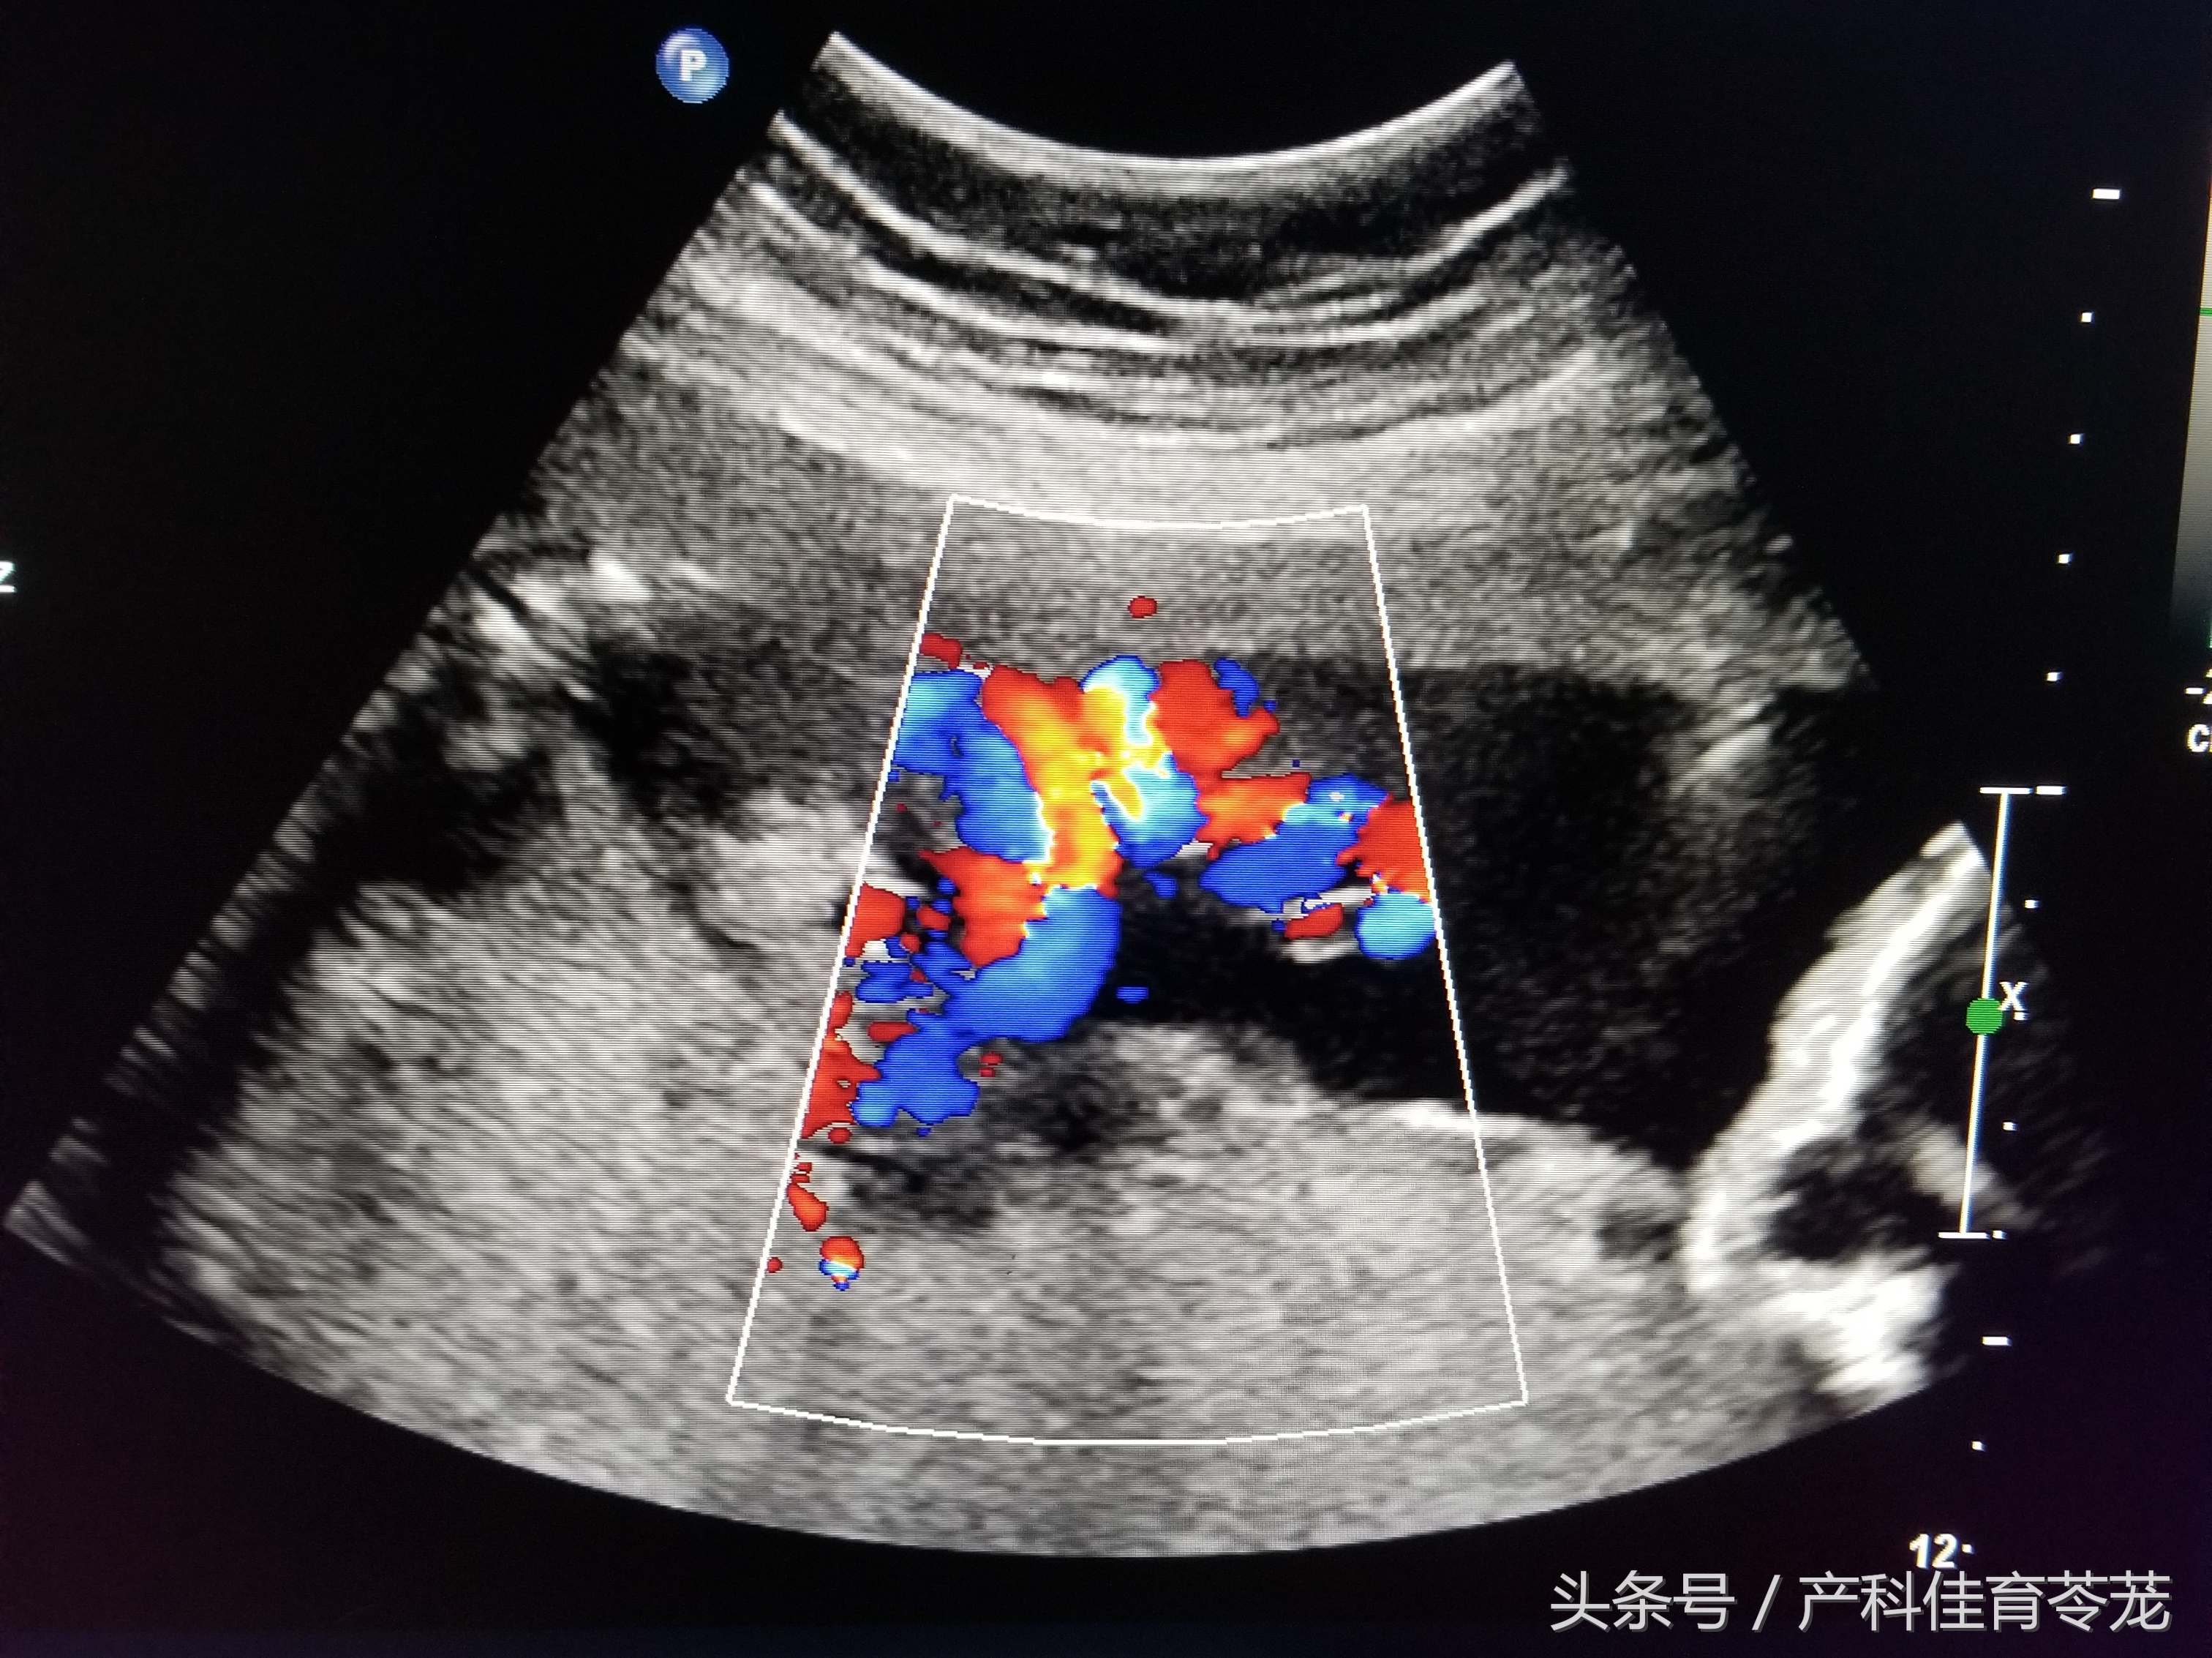

六、胎儿脐动脉血流

b超的3组数字代表什么,b超图片上的数字

在妊娠中晚期,可以用脐动脉的多普勒血流参数来评估胎盘循环,判断是否存在胎儿发育迟缓、判断是否存在胎儿缺氧。另外,胎儿如果有染色体异常、先天畸形等,脐血流有时也会表现出异常。

一般来说,B超会告诉您下列三个值:

PI——博动指数;

RI——脐动脉血流阻力指数;

S/D——脐动脉血流速度峰谷比。

数值多少与怀孕的周数有关,妊娠28周以后,S/D大于3.0或者RI大于0.6表示血流阻力加大,血液速度变慢,胎盘供血受限 ,胎儿有可能缺氧了。

注意:根据脐血流判断胎儿是否异常不是那么简单,还需要根据其他指标来综合判断,单纯的S/D高于正常不要过于恐慌,不一定代表异常。